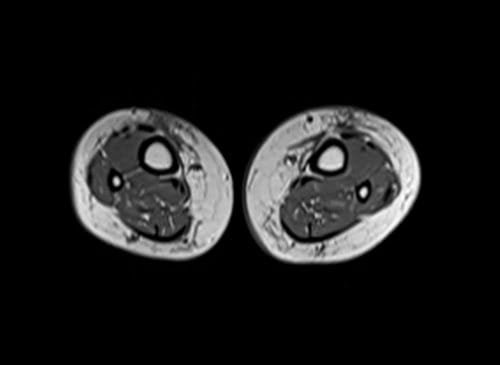

mri lower legs (calves) t1 axial image 1 - MRI